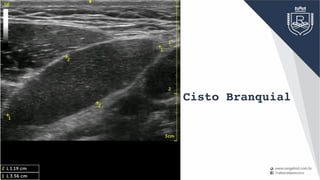

diagnóstico

programação

intra-operatório

Cisto Branquial